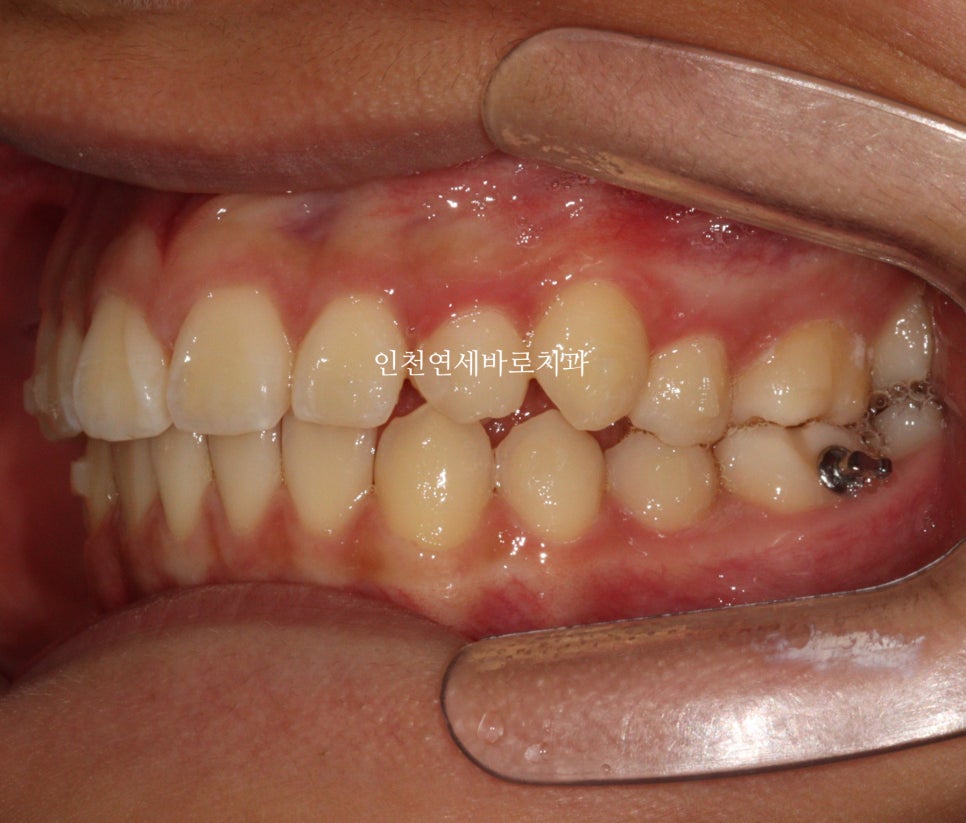

첫 번째 세트 완료 및 마무리 단계

첫 셋트가 끝났을 때 모습입니다.

위에 있던 치아는 자연맹출을 유도했는데 꽤나 그럴싸한 배열이네요

마무리를 간단하게 시작합니다.

마무리는 장치가 몇개 없이 해결되었습니다.

생각보다 자연맹출도 너무 예쁘게 되었네요

공간을 정확하게 배열해준 덕분이라 생각합니다